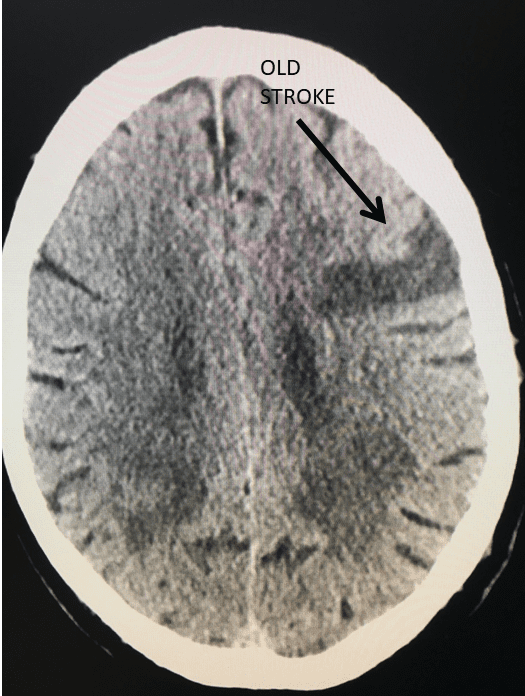

Figure 4.

Catheter angiography prior to angioplasty revealed critical stenosis (Figure 2). Angioplasty was therefore performed under local anesthesia with an embolic protection device deployed to catch any dislodged debris (Figure 3). After angioplasty, a stent was opened across the lesion to maintain long-term patency (Figure 4). Post-stent angiography showed smooth dilatation of the lesion. The patient’s aphasia continued to improve at his 6-week follow-up visit and duplex revealed no significant stenosis through the stent.